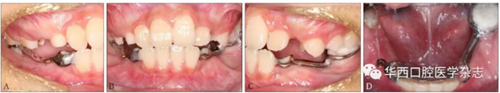

經(jīng)過綜合分析及考慮患者的意愿,制定開窗-正畸協(xié)同治療方案,術前拔除尚未萌出的45牙為牽引46牙提供間隙,通過鑄造板將36、73、32、31、42、41、83牙連接成一整體,為牽引46牙提供支抗(圖4)。

A:右側像;B:正面像;C:左側像;D:下頜面像。

圖 4 矯治器初裝口內(nèi)像